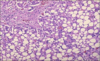

What normal endogenous substance is shown accumulated in this liver?

Triglycerides in liver of alcoholic

indicates reversible injury